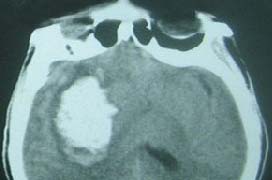

腦出血,俗稱腦溢血,屬于“腦中風(fēng)”的一種,是中老年高血壓患者一種常見(jiàn)的嚴(yán)重腦部并發(fā)癥,是指非外傷性腦實(shí)質(zhì)內(nèi)血管破裂引起的出血,常見(jiàn)的病因是高血壓、腦動(dòng)脈硬化、顱內(nèi)血管畸形等,常因用力、情緒激動(dòng)等因素誘發(fā),故大多在活動(dòng)中突然發(fā)病,臨床上腦出血發(fā)病十分迅速,主要表現(xiàn)為意識(shí)障礙、肢體偏癱、失語(yǔ)等神經(jīng)系統(tǒng)的損害。目前世界逐漸步入老齡化,腦出血已成為一較為廣泛發(fā)生的急癥重癥,我國(guó)每年因?yàn)槟X出血死亡的患者約占全部疾病死亡的20%左右,嚴(yán)重威脅人們的健康。

治療腦出血主要采用定向軟通道技術(shù)和顱內(nèi)血腫微創(chuàng)清除術(shù),效果令人滿意;颊呔唧w選擇哪種療法,需要結(jié)合患者病情和臨床醫(yī)師的診斷。